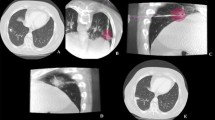

All thermal ablation treatments were performed via percutaneous approach, under CT guidance, using the HS AMICA™ 2.45-GHz microwave ablation system HS Hospital Service SpA), composed of a solid-state microwave generator with output of up to 140 W (AMICA-GEN, either model AGN-H-1.0 or AGN-3.0), and 14 G internally cooled interstitial applicators (AMICA-PROBE). A single antenna was used in all MWA treatments (Figs.1 and 2).

A 74-year-old man with a 2.8-cm primary tumor in the right upper lobe treated with MWA (60W × 10 min) (a, d: pre-procedural CT-images) with a large ablation volume obtained at 1-month follow-up (b, e: 1 month CT images). Primary tumor disappeared at 6 months follow-up CT images (c, f), without procedural nor delayed complications

A 70-year-old female with two 3-cm metastases in the middle (a), and right lower lobe (b), treated with MW ablations (70 W × 10 min), in supine (c) and right lateral-prone (d) decubitus, respectively. Apparent complete ablation of both tumors obtained at 1-month post-treatment CT scan, with sufficient safety margin without procedural complications (e, f). At 9-month CT follow-up, complete ablation was maintained in the peripheral metastasis (g), while a recurrence occurred on the hilar side of the central lesion, possibly due to heat sink effect of relatively large adjacent vessels (h)

Each lesion was treated inserting the antenna along the major lesion axis, placing the tip 1 to 5 mm beyond the tumor distal edge in order to obtain a sufficient (5–10 mm) safety margin (Fig. 2). Treatment protocol was standardized to continuous MW energy delivery at a pre-defined power rate (P) for a pre-defined time (T = 10 min), without neither probe re-positioning nor power variations during the treatment. P was pre-determined based on the lesion histology (considering that primary lung tumors need a wider safety margin than metastases [10,11,12,13]) and size, namely P = 40 W-60 W-80 W for treating tumors belonging to groups 1-2-3 of the MALT1 arm and P = 30 W-50 W-70 W for treating tumors belonging to groups 1-2-3 of the MALT2 arm. Treatment protocols were selected to warrant full coverage of the nodules (including the required safety margin) and equal energy delivery (Ed = P*T in seconds) in all lesions belonging to the same study group (Ed = 24 kJ-36 kJ-48 kJ for groups 1-2-3 of MALT1 and Ed = 18 kJ-30 kJ-42 kJ for groups 1-2-3 of MALT2). In the case of patients with multiple lesions, these were treated in the same session if located in the same lobe or lung (Fig. 2), or in separate sessions otherwise. All procedural data tracked by the generator during MWA procedures were recorded and attached to the correspondent case report form.

Post-treatment and follow-up studies

All patients underwent an unenhanced chest CT scan immediately after the removal of the antenna and a baseline and contrast-enhanced chest CT scan within 48 h post-MWA, to assess volume of ablation (V0) and exclude complications. Post-treatment chest CT scans and clinical examinations were scheduled at 1, 3, 6, 12, 18, and 24 months post-MWA, according to our standard of care, for the evaluation of the local efficacy and possible delayed complications (Figs. 1 and 2).

Based on the follow-up CT scans, treatment efficacy was evaluated as complete ablation (CA) (Figs. 1 and 2) or partial ablation (PA), according to CT analysis of lesion size and absence or persistent enhancement. Persistence or appearance (after CA) of enhancing areas was classified as LP (Fig. 2). Local and distant disease progression rates (LPR and DPR, respectively) and time to local and distant progression (TLP and TDP) were recorded. Finally, OS and LPFS curves were estimated.